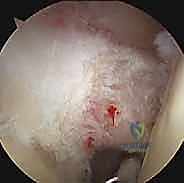

* التصوير بالرنين المغناطيسي (MRI): هو المعيار الذهبي للتشخيص. يوفر صوراً تفصيلية ثلاثية الأبعاد تظهر بدقة متناهية درجة الالتهاب، سماكة الوتر، وجود تمزقات جزئية، وحالة الأنسجة المحيطة مثل الكفة المدورة والشفا الحقاني.